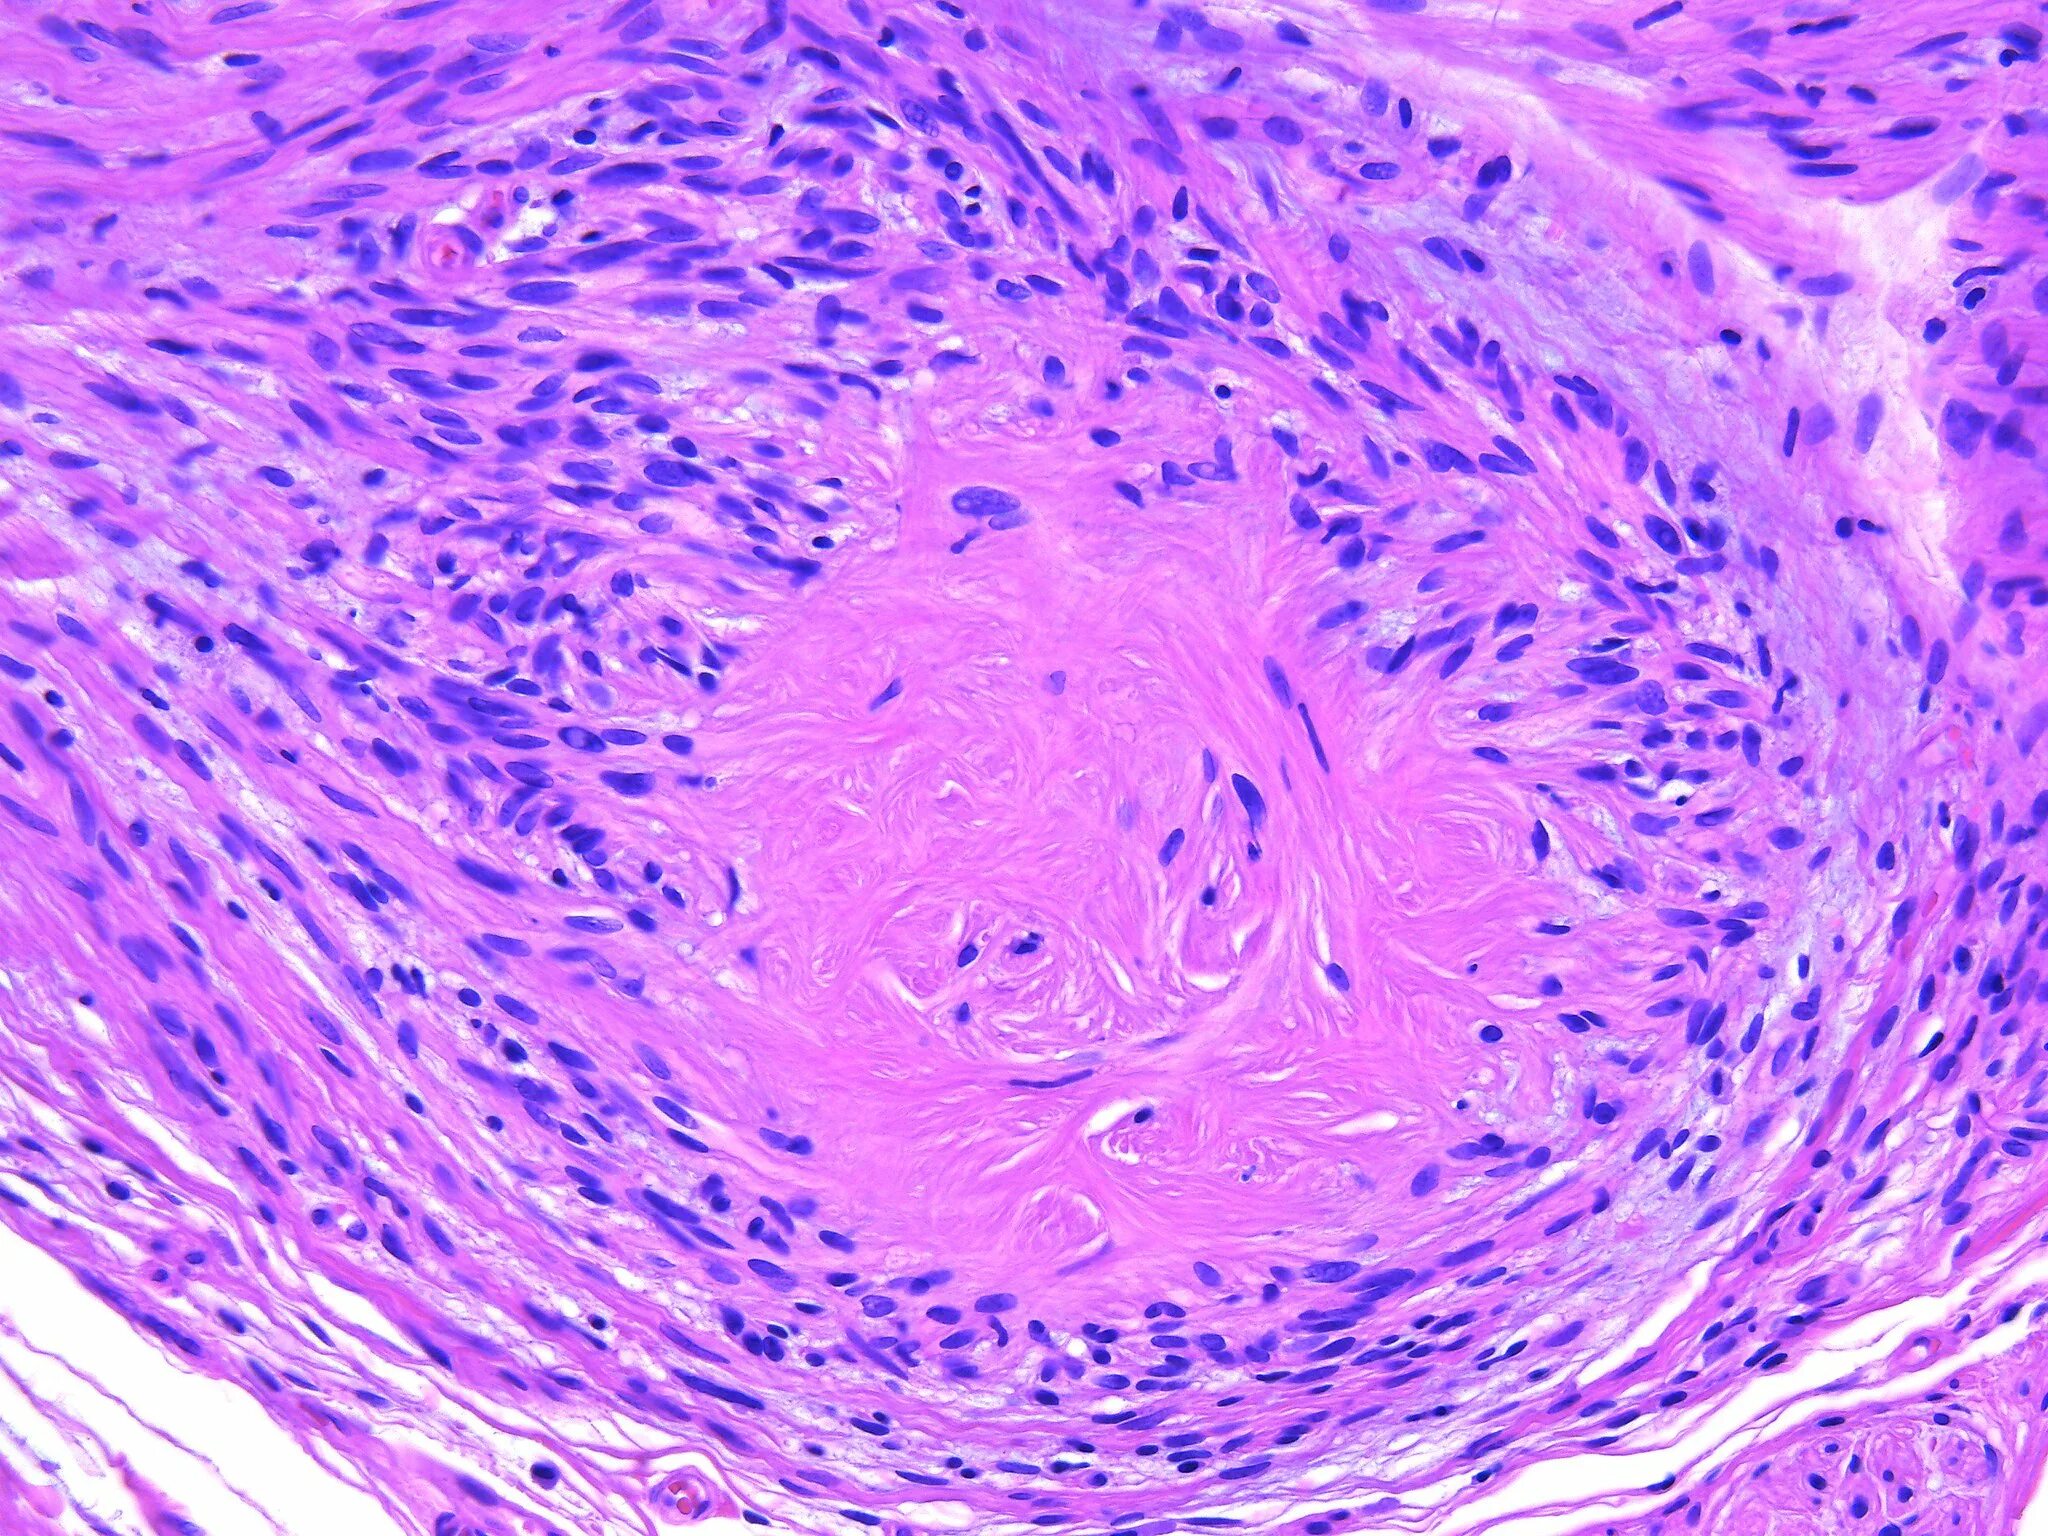

Молекулярная гистология